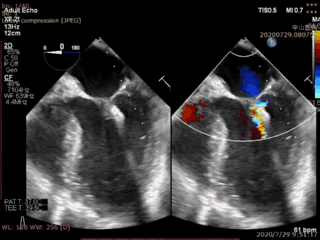

本例患者是一名70岁男性,术前超声心动图显示二尖瓣后叶冗长(前叶长度26mm,后叶长度20mm),瓣环前后径32mm,后叶p2关闭脱垂、连枷(脱垂宽度16mm,反流面积23.5cm2)。如此广泛的脱垂,使用国外同类产品完成经导管二尖瓣修复也是有极大挑战,经葛均波院士团队评估,多学科充分讨论后决定为该患者实施Valve Clamp二尖瓣夹合术。

首先在食道超声引导下,植入1枚IIIs型二尖瓣夹合器,释放后显示二尖瓣后叶仍有脱垂连枷,反流为轻中度,为改善患者远期疗效,遂再次植入1枚IIs型二尖瓣夹合器于A2P2的后瓣残余分流处,复查超声显示二尖瓣反流完全消失(0级),整个手术切口出血量几乎为零,手术取得圆满成功。